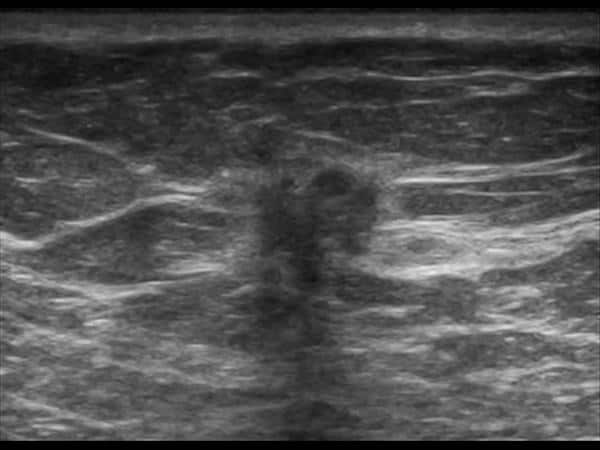

Ung thư vú

Ung thư vú - Ảnh 2

Ung thư vú - Ảnh 3

Ung thư vú - Ảnh 4

Ung thư vú - Ảnh 5

» Thông tin: Nữ giới – 71 tuổi.

» Lâm sàng: Khối tuyến vú.